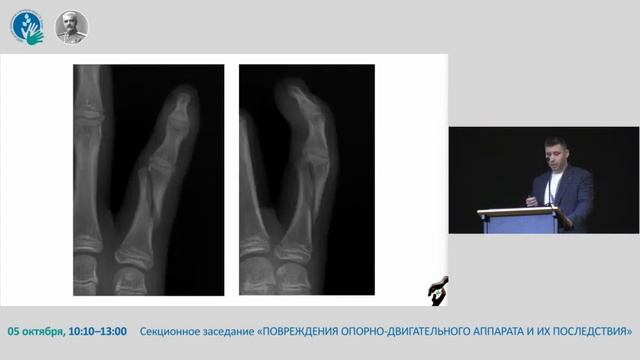

Особенности остеосинтеза фаланг пальцев кисти у детей.

Видео Особенности остеосинтеза фаланг пальцев кисти у детей.